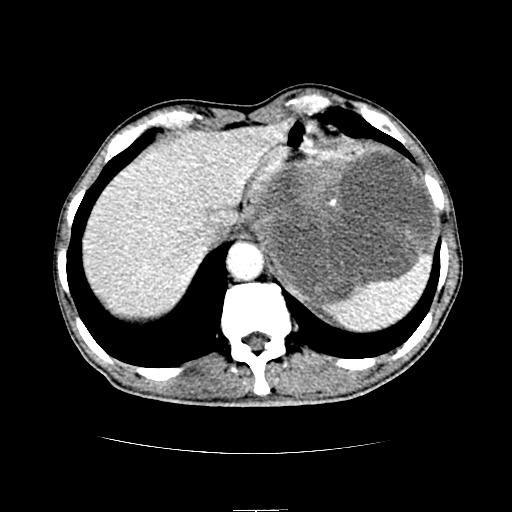

标题: CT6969:腹部,某男 34岁,腹痛治疗半月无效 [打印本页]

标题: CT6969:腹部,某男 34岁,腹痛治疗半月无效

左上腹胃、脾及胰腺间巨大囊性占位性病变,内见多数薄隔,有轻度强化,明显占位效应。左肾见一小囊肿。

考虑:1、左上腹巨大囊肿(可能来源于胰腺)。

2、左肾小囊肿。

左上腹胃、脾及胰腺间巨大囊性占位性病变,内见多数薄隔,有轻度强化,明显占位效应,胰腺及左肾结构清楚,明显向后下方推压 移位。左肾见一小囊肿.多考虑:1 网膜巨大囊肿。2 左肾小囊肿。

1胃脾胰之间一巨大囊性影,胃明显向前推移,胰体尾部似肥大,考虑囊性影来源于胰腺(假性囊肿?)2左肾小囊肿。

左上腹囊性占位,与胰腺分界不清,考虑起源于胰腺可能。

左上腹囊性占位,虽与胰腺分界不清,胰尾似乎受压前移,病灶最大截面并不在胰腺水平,考虑来源于网膜可能性大吧,应再详细追问病史.